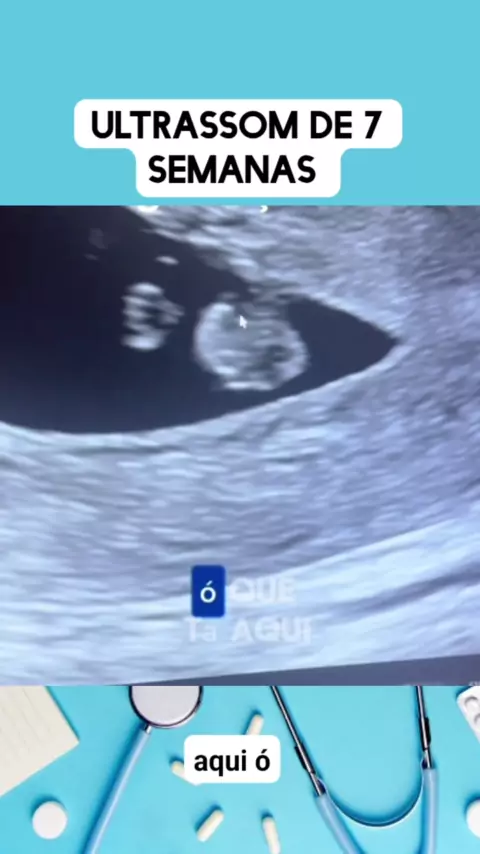

ultrassom de 7 semanas #medico #medicina #Saúde #viraliza